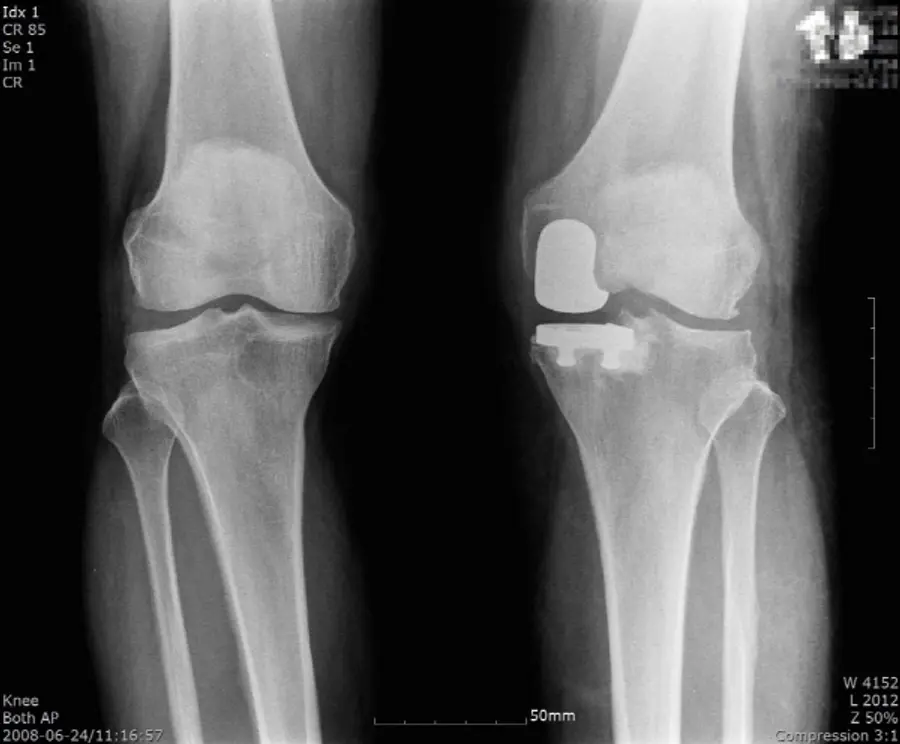

초기와 중기에는 약물치료나 주사치료, 도수치료 등으로 통증을 조절하고 줄기세포 치료 등을 병행해 연골 재생을 기대해볼 수 있다. 그러나 보존적 치료만으로 증상이 호전되지 않거나, 연골이 모두 닳아 없어진 말기에 이르러 더 이상의 치료 효과를 보기 어려울 때는 무릎 관절을 교체하는 인공관절수술을 진행하게 된다.

인공관절수술은 손상된 연골을 제거하고 인공관절을 삽입하는 수술이다. 타고난 관절 대신 인공구조물로 관절을 대체한다는 점 때문에 부담을 느끼는 환자들이 있지만, 인공관절 수술은 수술 후 치료 만족도가 높은 편이다. 수술 후 앉고, 걷고, 계단을 오르내리는 일상생활이 편안해지면서 건강한 생활을 되찾을 수 있기 때문이다.

관절 전체가 손상된 경우가 아니라면 관절을 전부 교체하는 전치환술 대신 건강한 관절을 최대한 보존하는 부분 치환술로 치료를 진행할 수 있다. 부분치환술은 관절 기능을 보존할 수 있고, 관절 운동의 각도가 좋은 것이 장점이며 절개와 출혈도 상대적으로 적기 때문에 회복도 빠른 편이다.

다만 부분인공관절 수술은 기존 인공관절 전치환술보다 까다로운 수술로, 무릎 관절을 구조물들의 원래 위치를 파악하고 환자의 관절 기능 향상을 위해 정밀한 검사를 통해 위치를 설정하여 수술이 이뤄져야 한다.